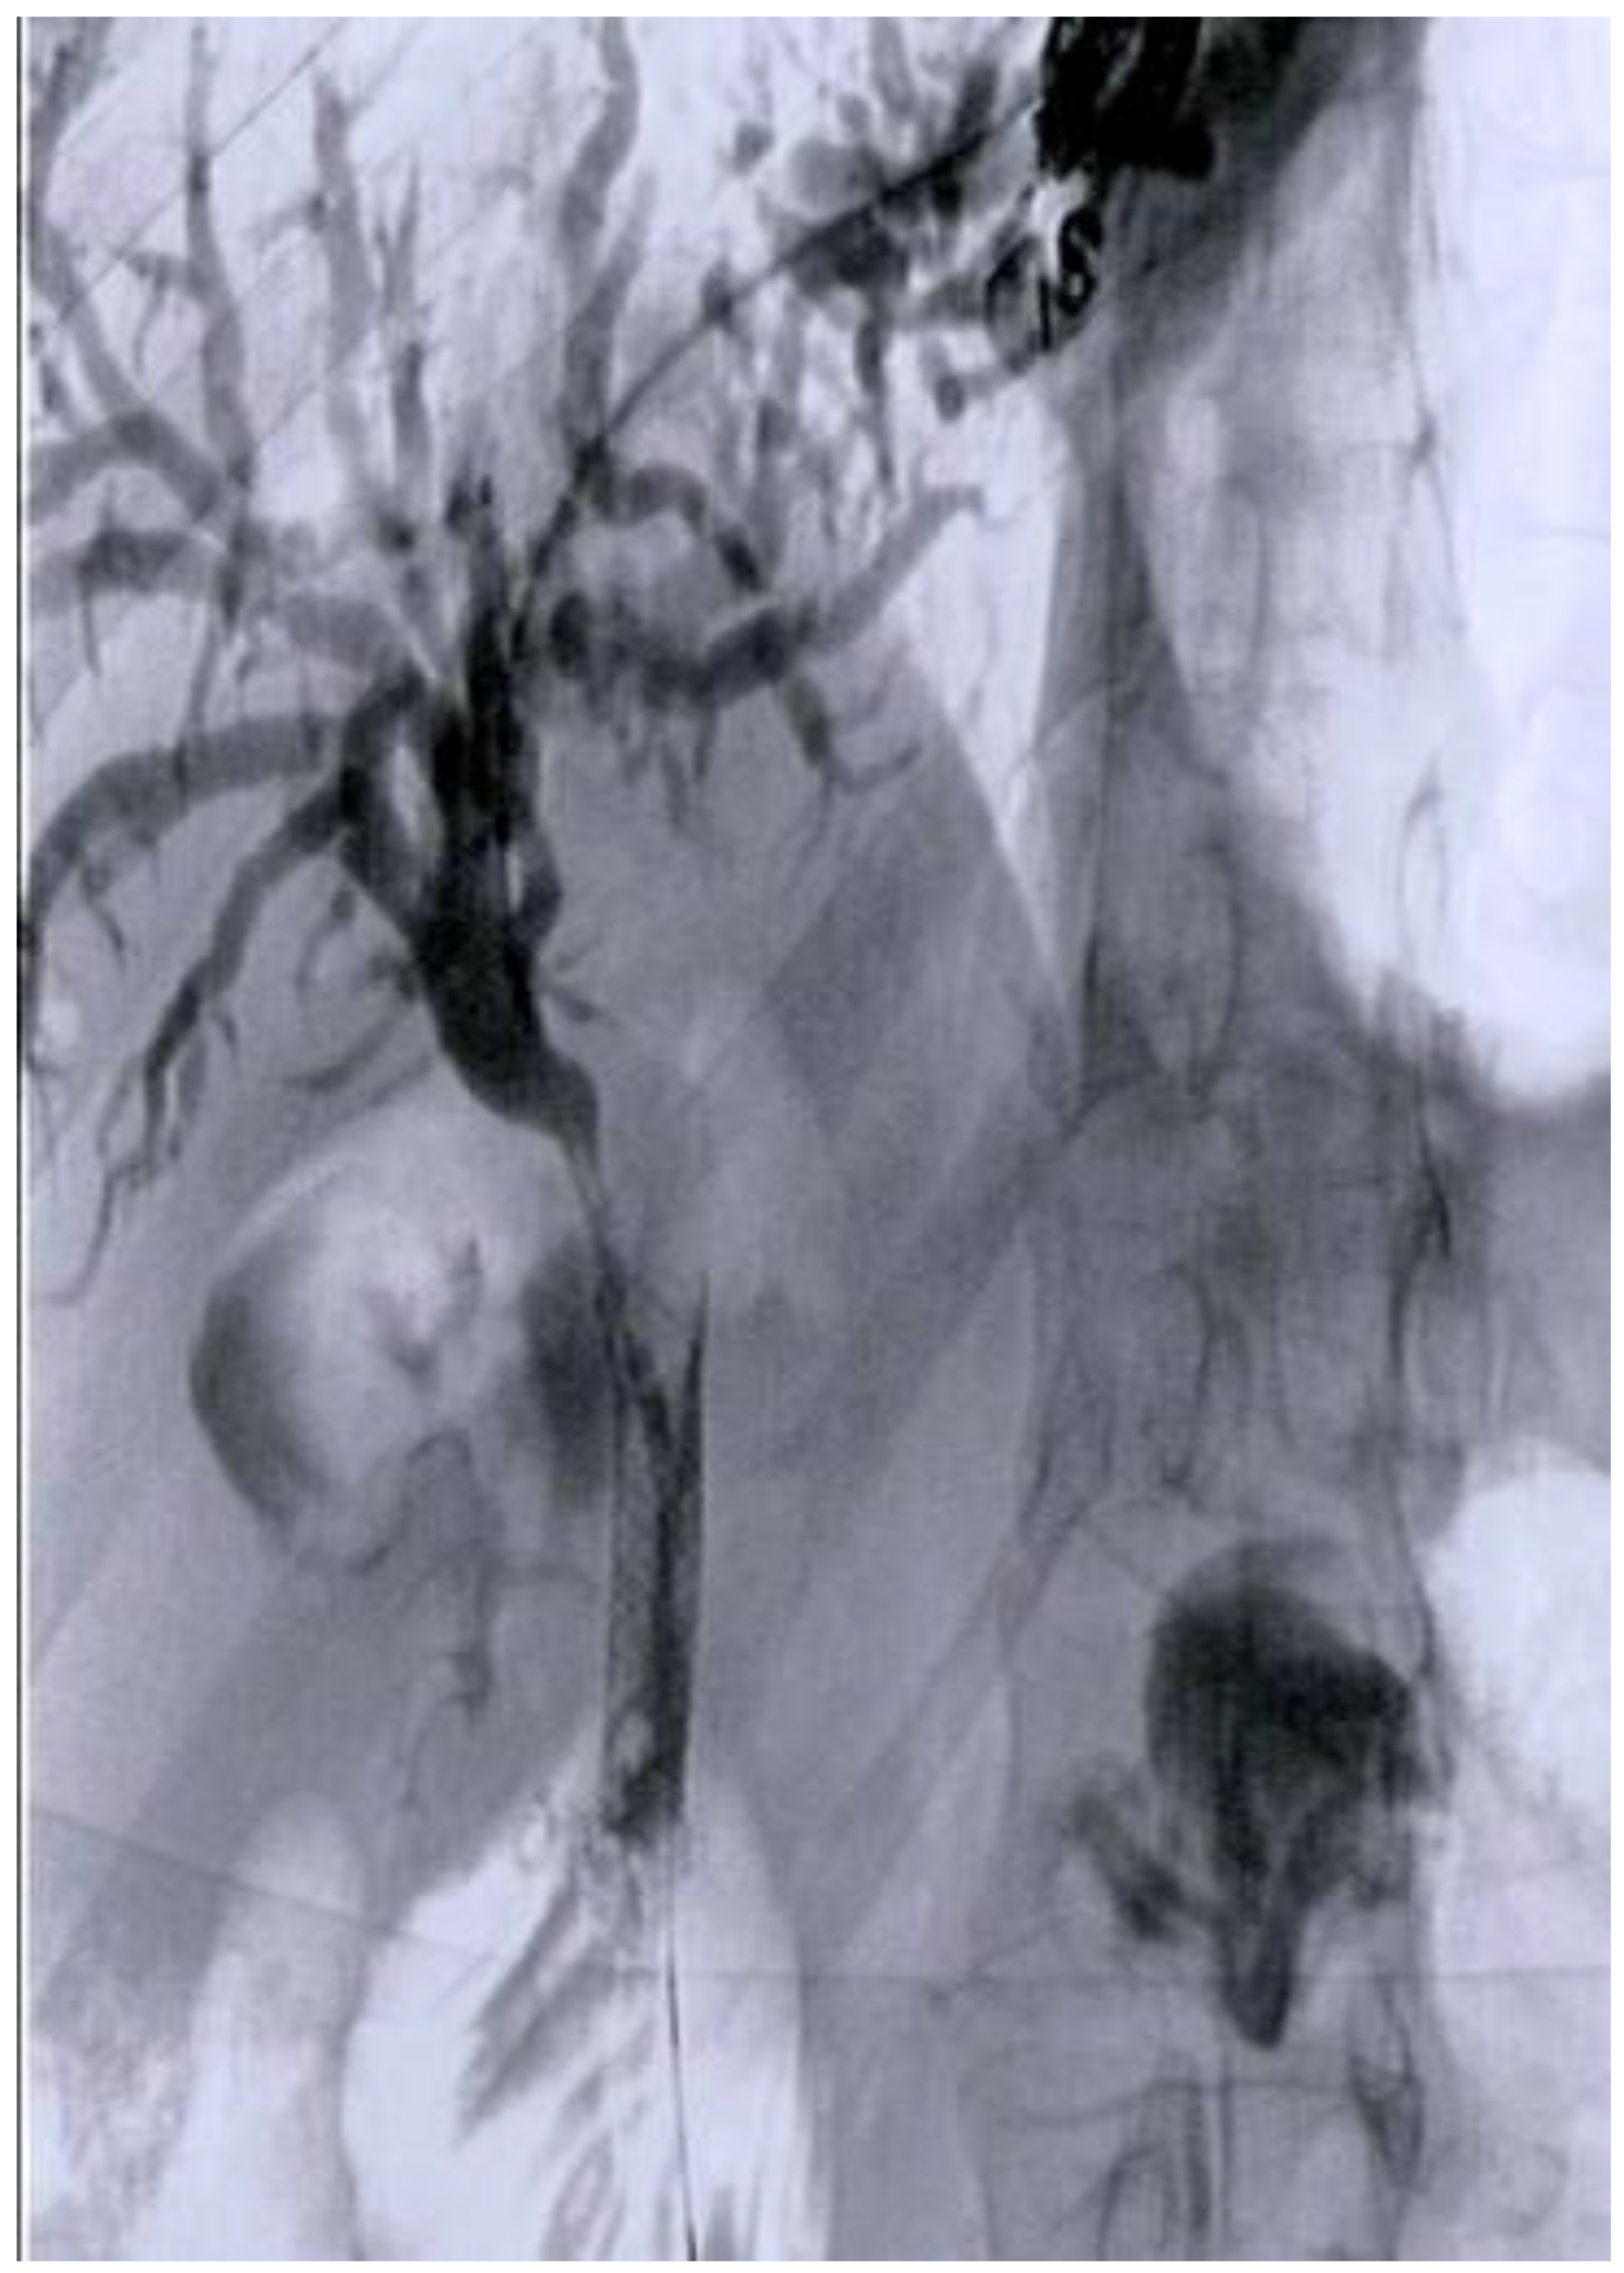

- Iwashita, T.; Yasuda, I.; Mukai, T.; Iwata, K.; Doi, S.; Uemura, S.; Mabuchi, M.; Okuno, M.; Shimizu, M. Endoscopic ultrasound-guided antegrade biliary stenting for unresectable malignant biliary obstruction in patients with surgically altered anatomy: Single-center prospective pilot study. Dig. Endosc. 2017, 29, 362–368. [Google Scholar] [CrossRef]

- Iwashita, T.; Uemura, S.; Mita, N.; Iwasa, Y.; Ichikawa, H.; Mukai, T.; Yasuda, I.; Shimizu, M. Endoscopic ultrasound guided-antegrade biliary stenting vs percutaneous transhepatic biliary stenting for unresectable distal malignant biliary obstruction in patients with surgically altered anatomy. J. Hepatobiliary Pancreat. Sci. 2020, 27, 968–976. [Google Scholar] [CrossRef] [PubMed]

- Minaga, K.; Takenaka, M.; Ogura, T.; Tamura, T.; Kuroda, T.; Kaku, T.; Uenoyama, Y.; Noguchi, C.; Nishikiori, H.; Imai, H.; et al. Endoscopic ultrasound-guided biliary drainage for malignant biliary obstruction with surgically altered anatomy: A multicenter prospective registration study. Ther. Adv. Gastroenterol. 2020, 13, 1756284820930964. [Google Scholar] [CrossRef] [PubMed]